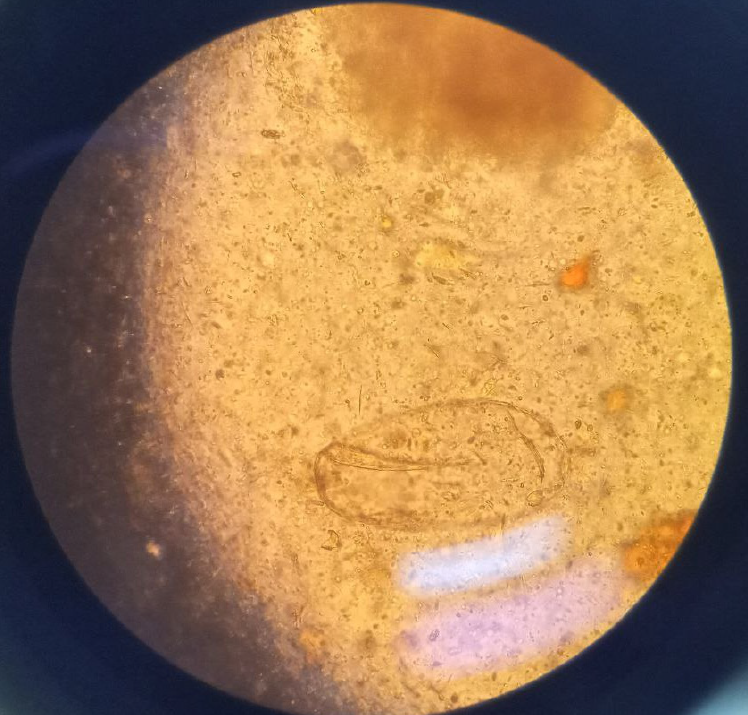

Figure 1 Microscopic visualization of a fasciola egg in a stool specimen.

This light microscopic image shows a single, large oval shaped egg with a thin, smooth, yellowish shell visualized under non stained wet mount stool preparation.